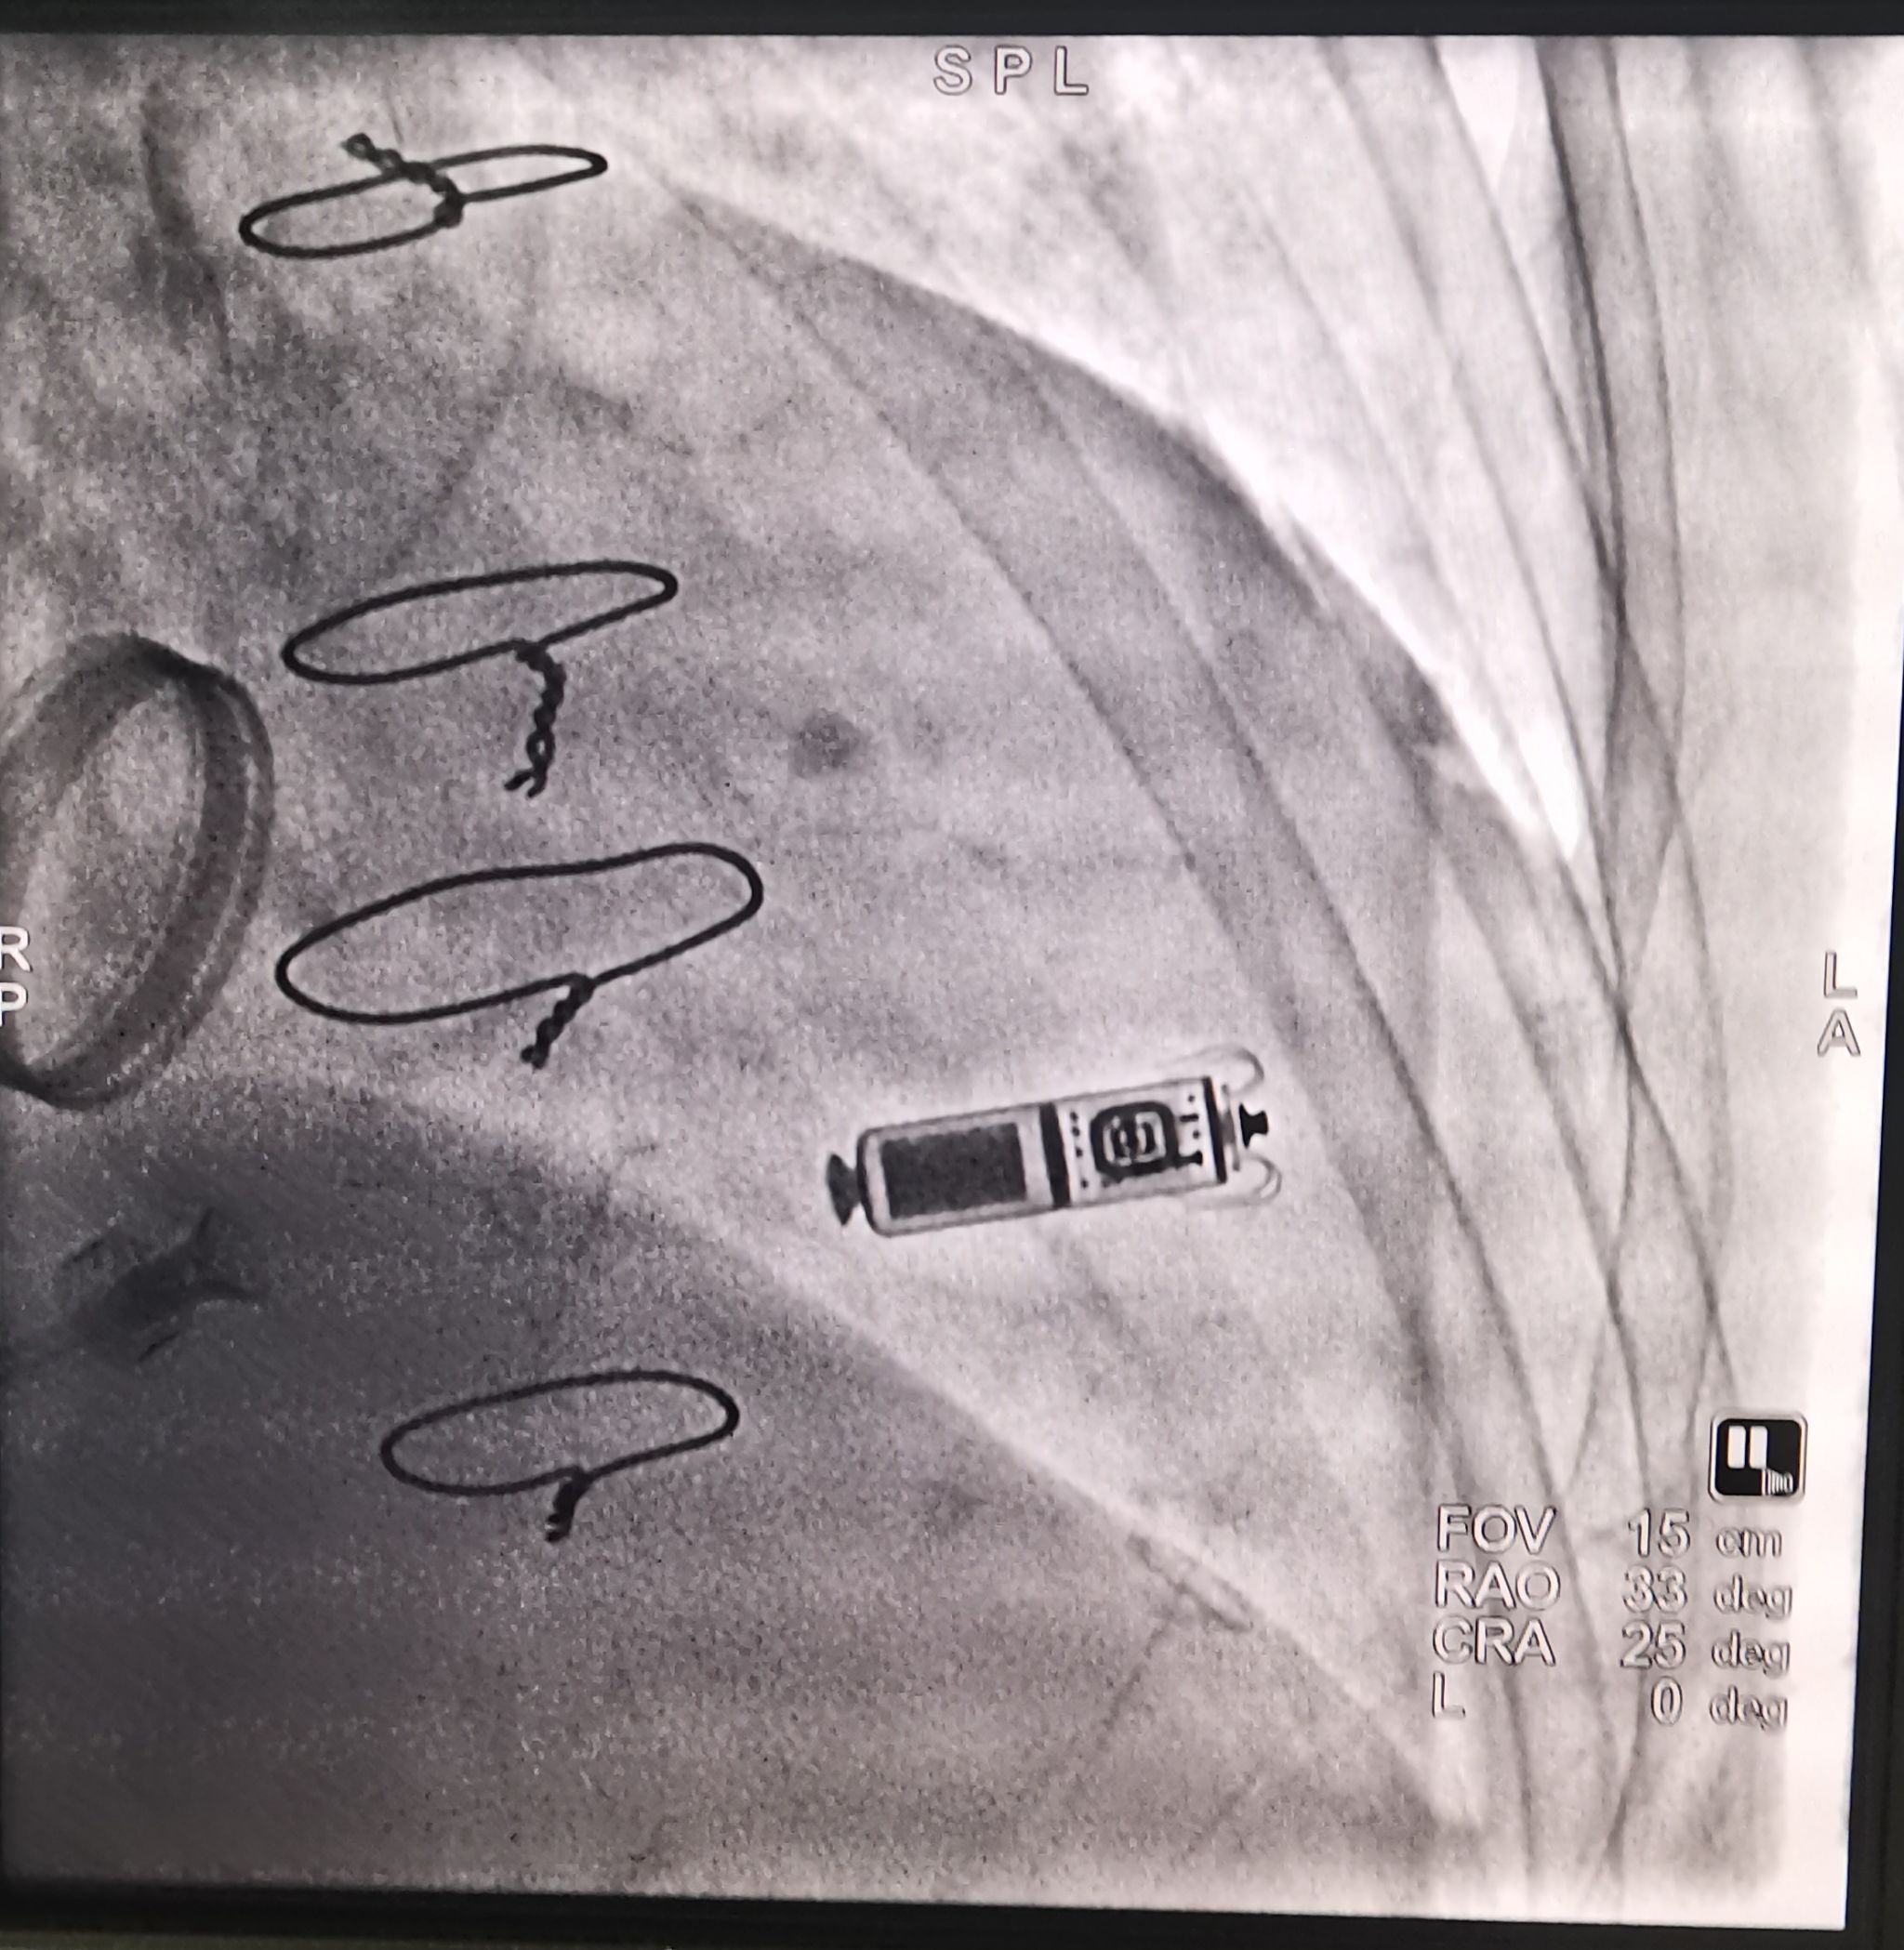

穿刺右侧股静脉送 Micra 递送系统经右心房跨三尖瓣送抵右室中位间隔区,造影见电极贴壁良好,原位释放起搏器,测试起搏参数:起搏阈值 1.0 V,阻抗 760Ω,感知 5.0mV。行牵拉试验示起搏器固定良好,剪断栓绳后撤出输送鞘管,缝合伤口予以加压包扎。术程顺利,术后心电监护及程控起搏器工作良好。